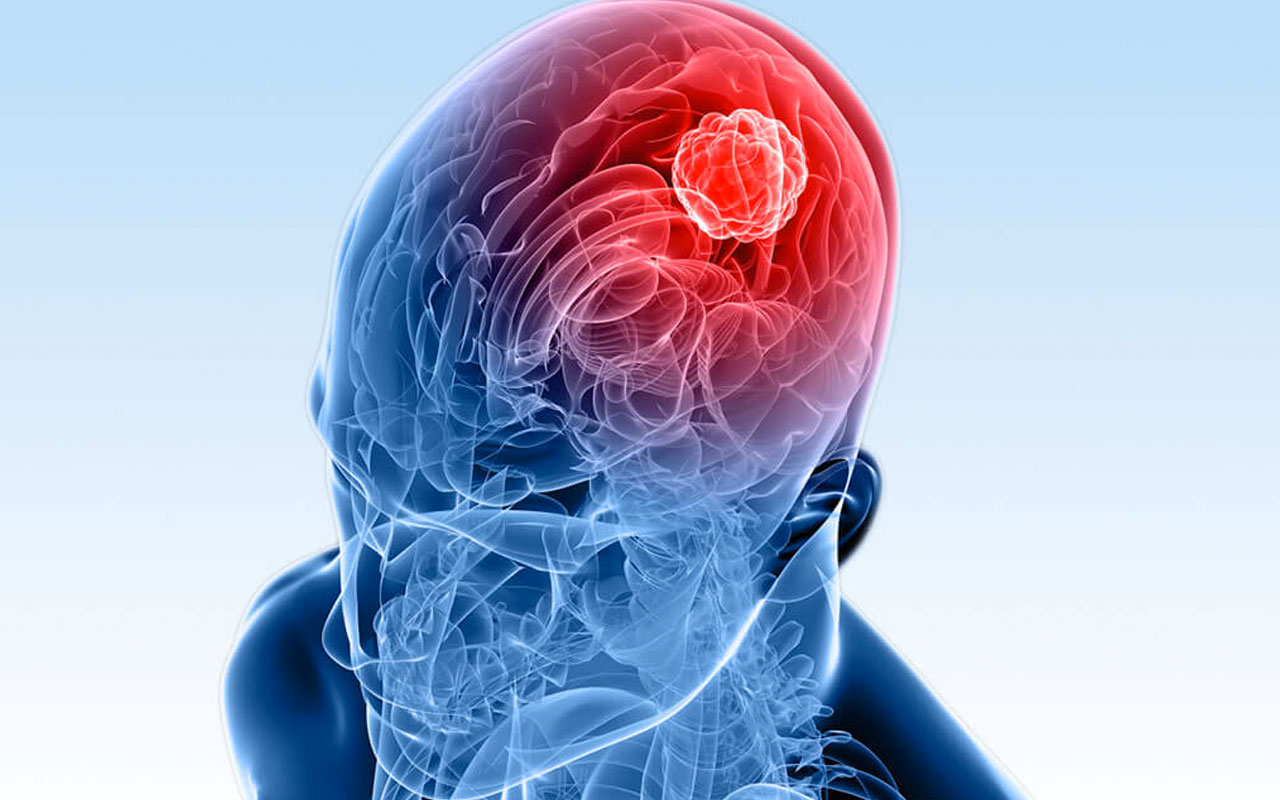

Beyindeki tümörlerin görme alanına baskısı durumunda ne olur?

Beyindeki tümörlerin görme alanına baskısı durumunda ne olur?

Göz muayenesinde bir şey bulunmadığı durumlarda gözün arkası muayene edilebilir. Optik sinirler başında müphem şeyler görülebildiğini anlatan Prof. Dr. Ferda Çiftçi bu durumda görme alanı testinin yapılması gerektiğini ve görme alanı ile ilgili olan hipofiz bezinin tetkik edilmesi gerektiğini belirtiyor.